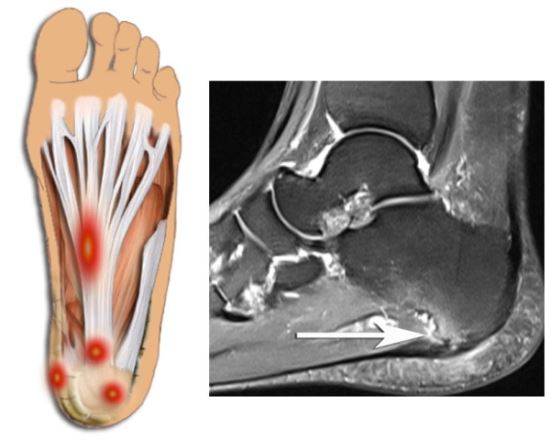

플랜타르 패시아염 (족저근막염)

- 발바닥의 아치에 위치한 두꺼운 섬유 조직인 족저근막이 염증이 생기는 질환입니다. 주로 장시간 서 있거나 걷는 경우, 혹은 비만으로 인해 과도한 압력이 가해져 발생합니다. 통증은 주로 아침에 일어났을 때 첫 발을 내딛을 때 가장 심하게 느껴지며, 점차 운동 후에도 나타날 수 있습니다.